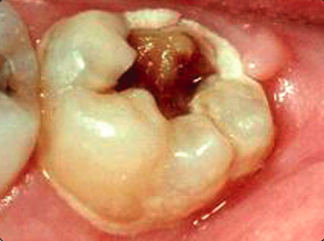

Caries opstår de steder på tænderne, hvor uforstyrret plak har fået lov til at sidde længst. Der kan ikke opstå caries i en ren tand eller på en ren tandoverflade.